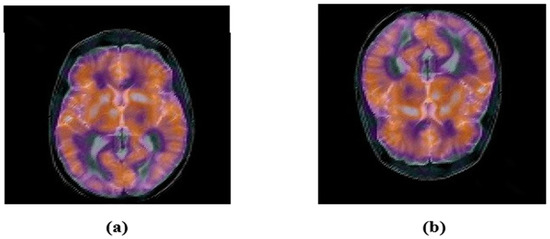

2.3. Accurate Computation of New Multi-Channel Gaussian-Hermite Moments of Color Images